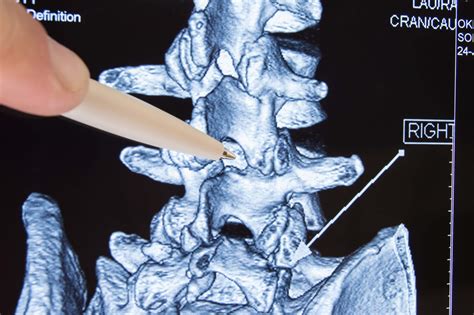

Diagnosing subluxation typically involves a combination of physical examination and imaging tests. A healthcare provider will perform a thorough evaluation to assess the spine's alignment and function. This may include:

• Imaging Tests: X-rays, MRI, or CT scans may be used to visualize the spine and identify any misalignments or abnormalities.